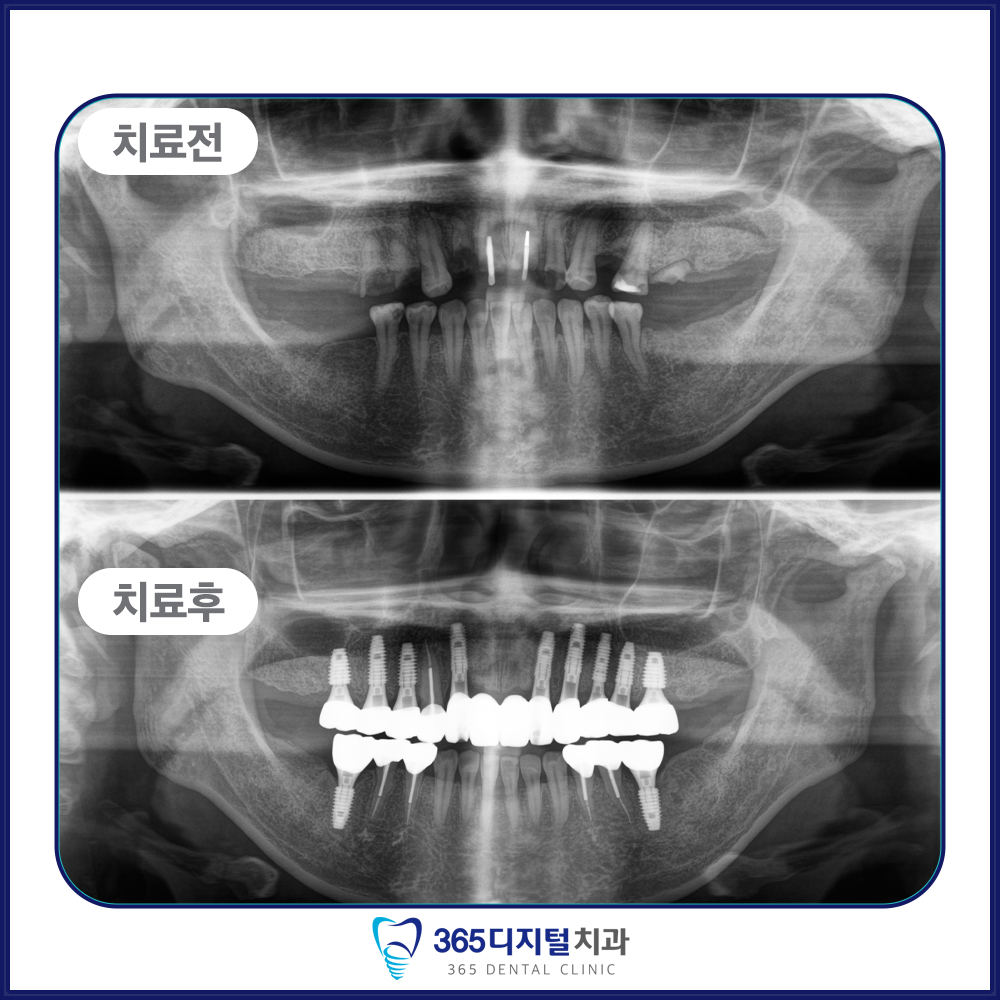

임플란트는 단순히 인공치아를 심는 것이 아닌,

환자의 삶의 질을 회복하는 진료라고 생각합니다.

오직 정밀한 진단과 정직한 진료만이

좋은 결과로 이어진다는 믿음으로

한 케이스, 한 환자에 깊이 집중합니다.

계획된 진단과 세밀한 설계,

그리고 환자 개인의 구강 구조에

맞춘 접근이 중요합니다.